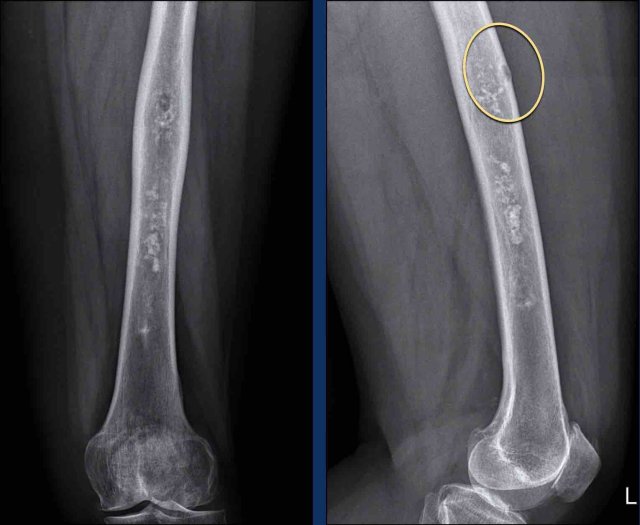

Case

First look at the images and decide whether you are dealing with an ACT or CS.

Then continue reading.

Images

There is a lesion measuring

more than 20 cm in the diaphysis of the femur.

Note the popcorn matrix

calcifications.

There

is one focal nodule (within the yellow circle) causing cortical scalloping and

there is mild extension of the marrow cavity.

Continue with the MR...

First look at the images.

MR-images show interspersed fat between the cartilage nodules.

It has a high signal on the sagittal T1W-image and low signal on the fat suppressed image (arrows).

There is one focal nodule causing cortical scalloping (<10%) and there is mild extension of the marrow cavity.

Conclusion

The lesion was diagnosed as ACT and remained

stable during follow up.